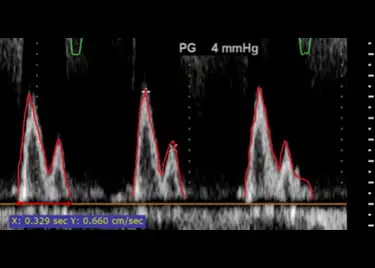

Deep-learning based analysis